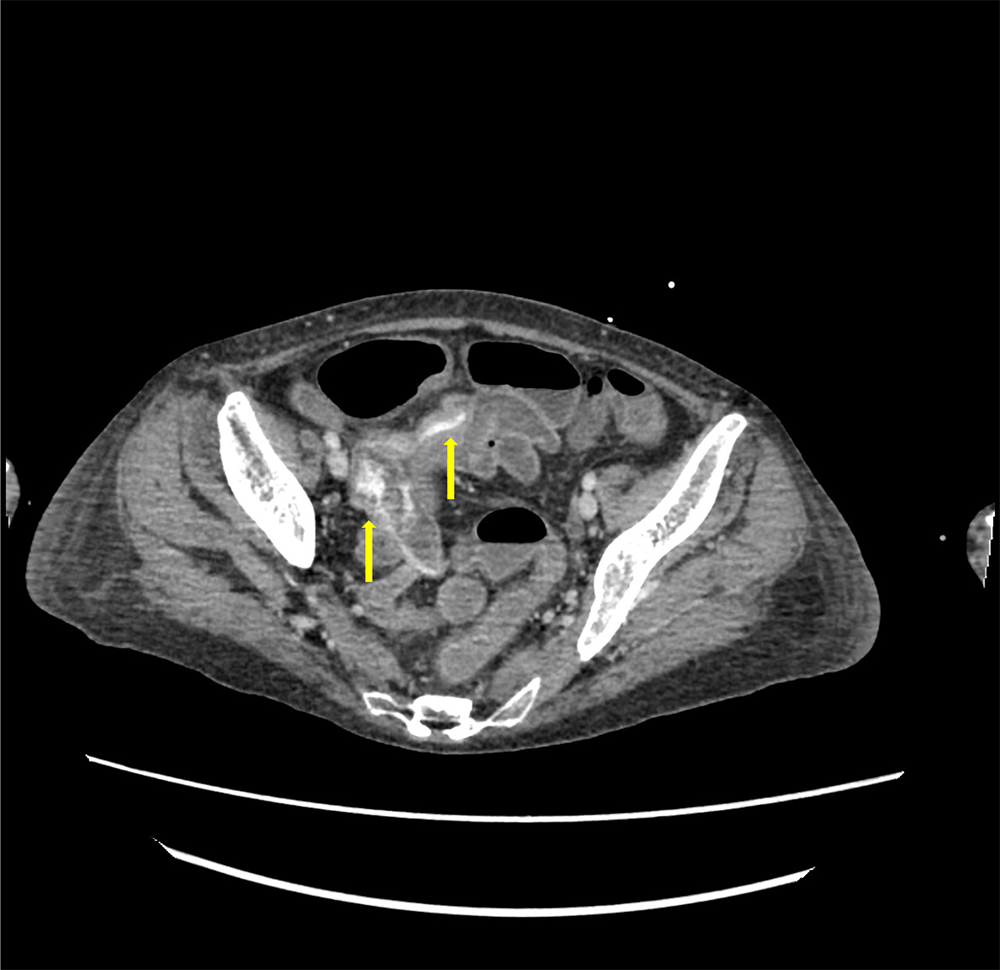

サイトメガロウイルス感染症を背景に下血がみられ消化管出血が疑われた。出血源の精査目的に造影CTが施行された。造影CTにて回腸で造影剤の血管外漏出像がみられ、出血源と考えられた。

消化管出血において、新鮮なものであれば単純CTで消化管内の血球成分が高吸収を示し、出血の有無については判別できることもあるが、出血源の同定はしばしば困難となりうる。この場合造影ダイナミックCTによる精査が必要となる。造影CTを撮像することで、出血源の同定や出血の程度を評価することができ、経カテーテル的血管塞栓術が検討される場合に責任血管までのアクセスルートも確認することが可能である。

撮影時の注意点として、造影CTのみを撮像してしまうと消化管内に高吸収を示す残渣や憩室内の糞石などがみられた場合に造影剤の血管外漏出像との判別が困難となることがあるため、同時に単純CTもあわせて撮像することで判別の補助となりうる。また下部消化管出血はしばしば間欠的に出血するため、造影CT撮像のタイミングで出血が止まっていれば出血源の同定が困難となることがあり、注意が必要である。